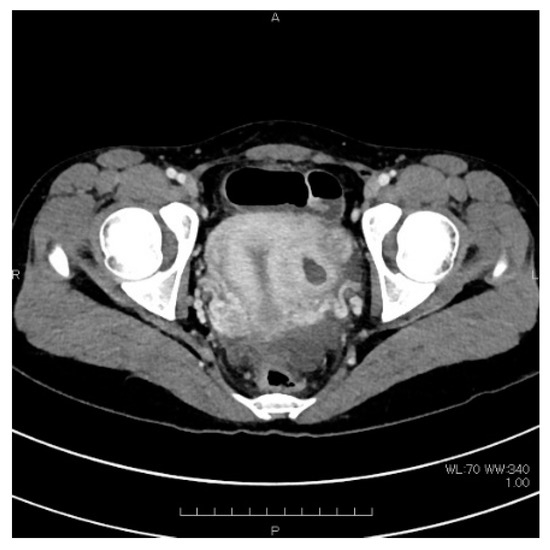

2. Case Presentation